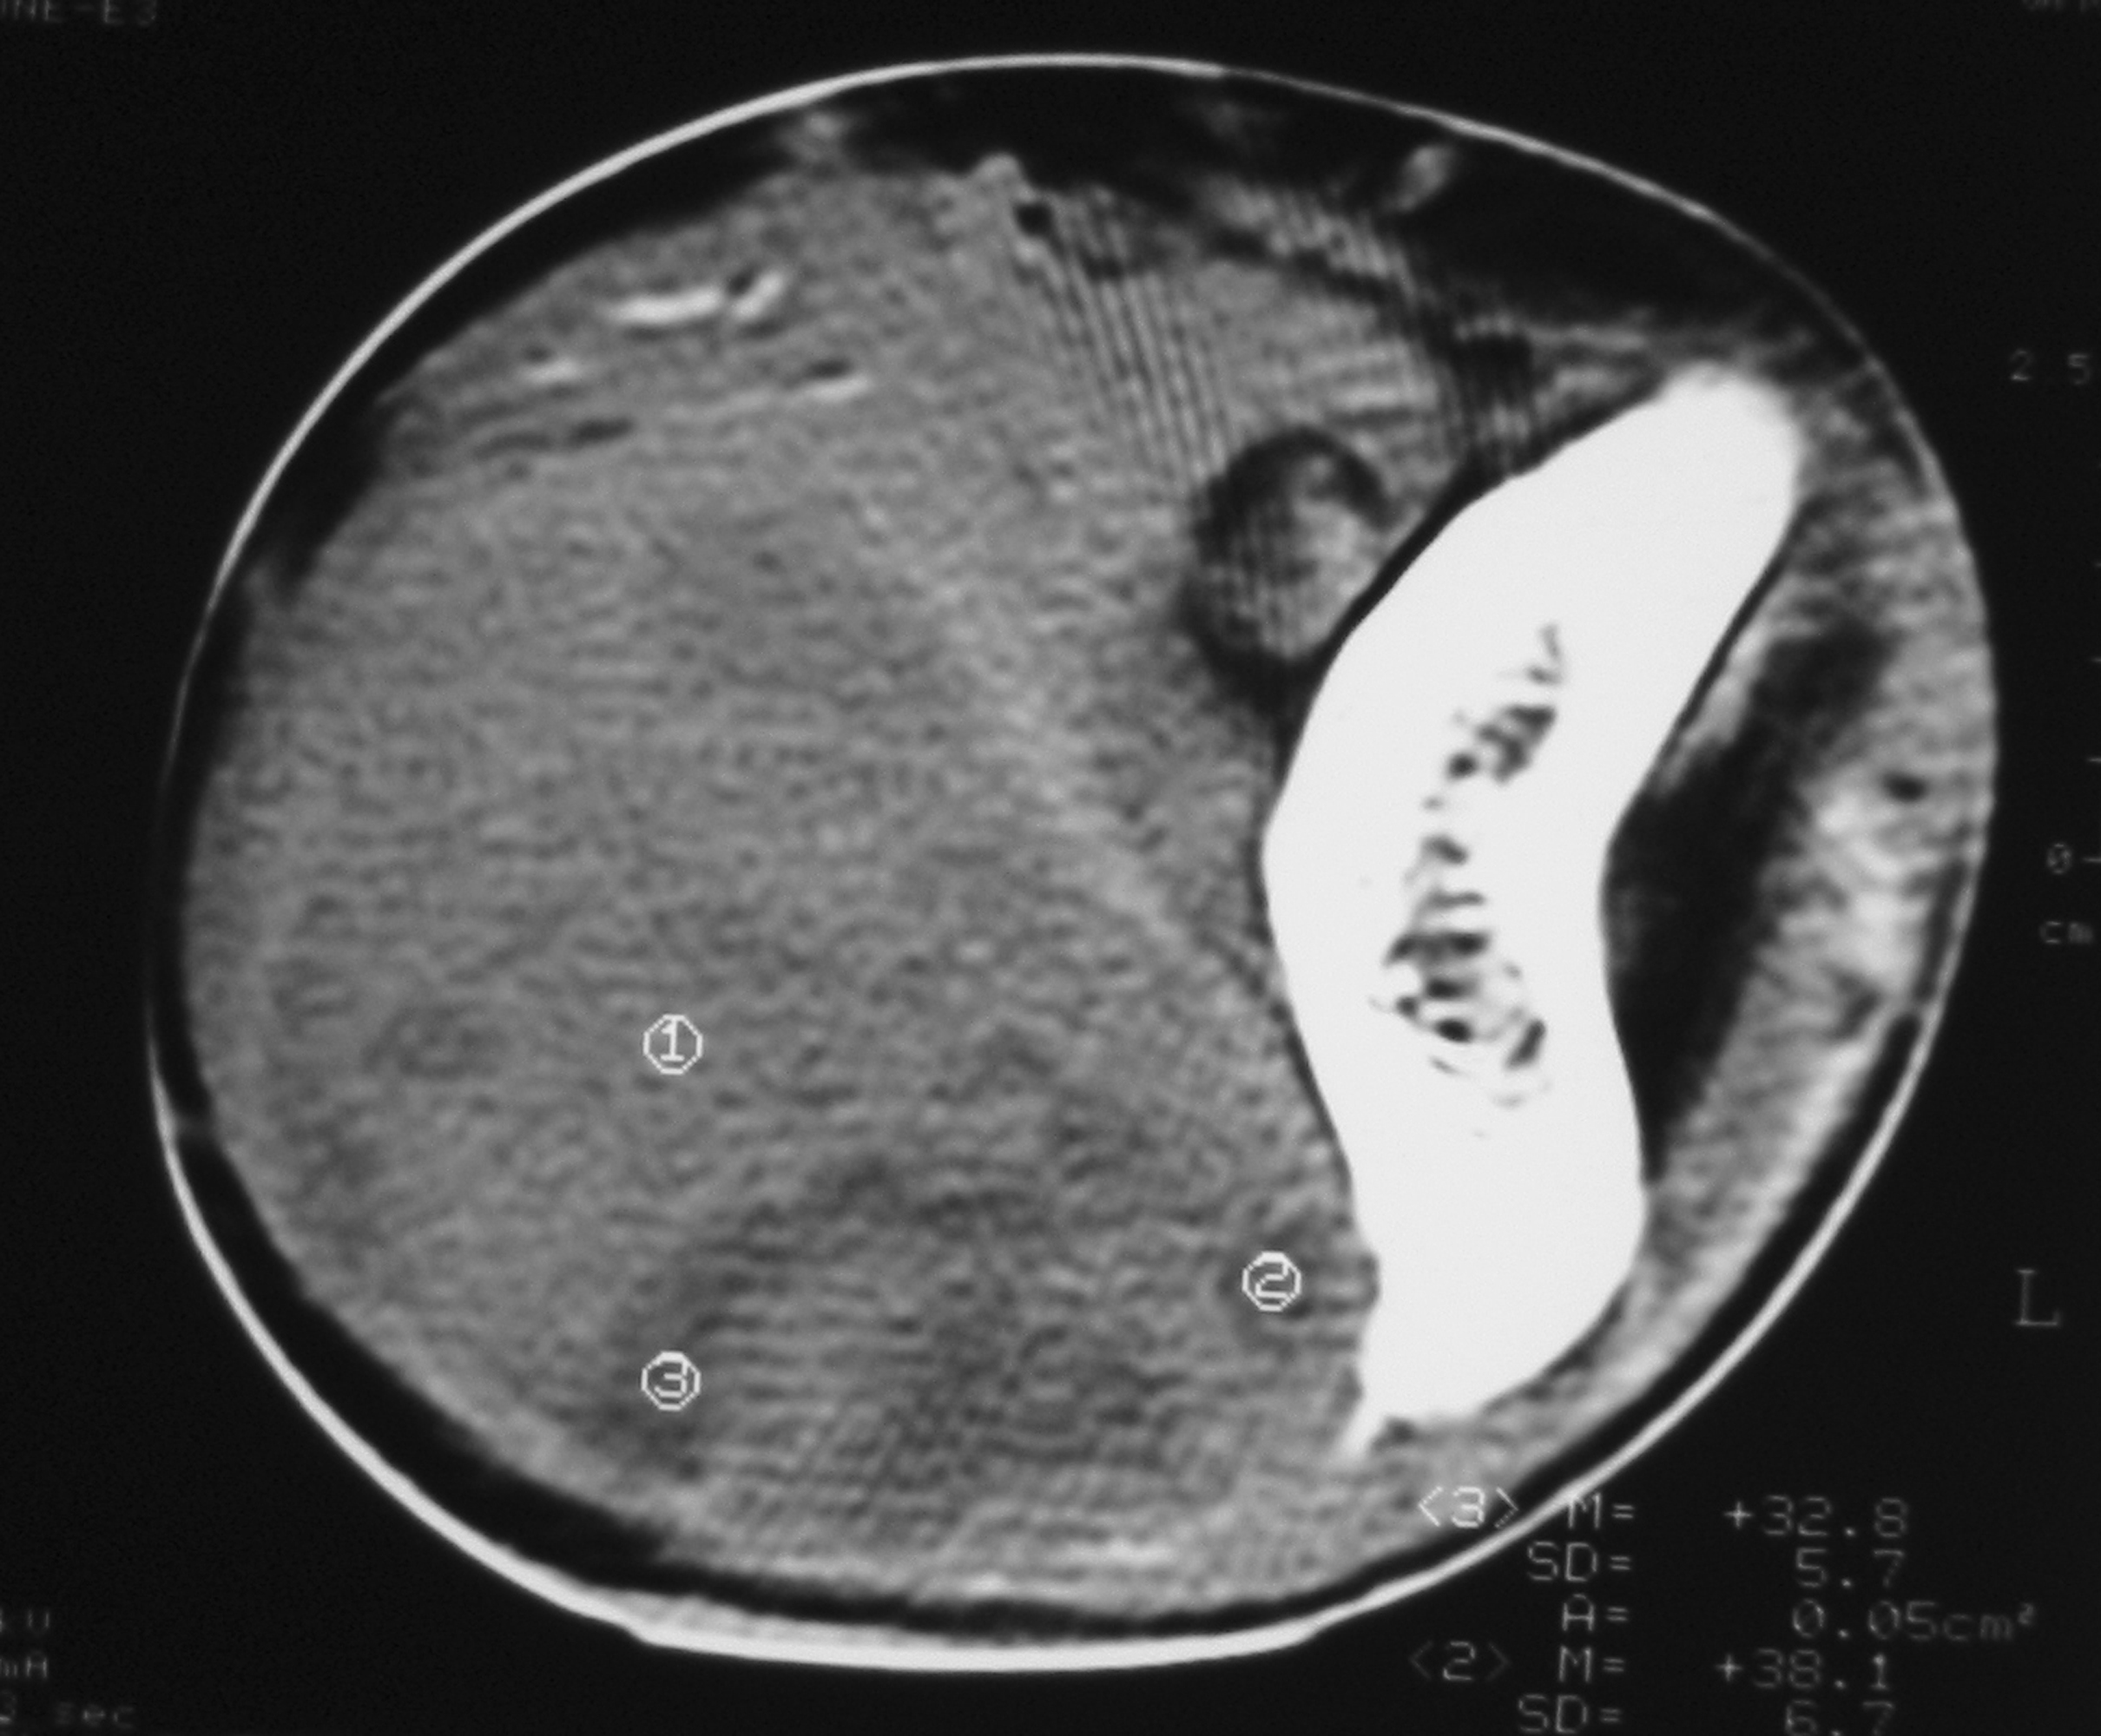

There were 6 females and 6 males (sex ratio 1 : 1) ranging in age from 6 to 47 years (mean age: 21 years). Eight cases occurred in patients less than 20 years of age. The tumors occurred predominantly in the lower extremity (10 cases: foot in 4 cases, thigh in 4 cases and calf in 2 cases), one case arose in the upper extremity (elbow) and one case in the hypopharynx. The primary presenting symptoms comprised a painful tumefaction in 6 cases, isolated pain in 3 cases, dysphagia in the case of oropharyngeal SS and cough and expectorations in one case of SS revealed by lung metastasis. In the remaining case, SS was revealed by traumatism of the affected area. The mean time from onset of symptomatology and pathological diagnosis of sarcoma ranged from 2 months to 6 years. Clinical examination showed a painful tumefaction, firm in consistency, fixed to the deep plan, without cutaneous signs. Standard radiographs of the tumors were made in all the cases and showed calcifications in 2 cases, a well defined opacity in 3 cases, bone invasion in 4 cases and were interpreted as normal in 3 cases. Echography, performed in 6 cases, was assessed as normal in 6 cases and showed a heterogeneous mass in one case and a hypoechoic mass in one case. Computed tomography studies were undertaken at the first presentation in 7 cases and showed a heterogeneous mass with heterogeneous vascular enhancement (Fig. 1), invading adjacent bone in one case; calcifications were observed in 2 cases and the diagnosis of SS was suspected in one case. Magnetic Resonance Imaging (MRI) examination was performed primarily in 3 cases and showed a well defined mass enhancing asymmetrically after gadolinium injection (Fig. 2). The neoplasms were hypointense on T1-weighted MR images and hyperintense on T2-weighted MR images, vascular invasion was seen in one case and the diagnosis of SS was suspected in one case.

![]() Click for large image | Figure 1. Unenhanced computed tomography image showing a solid soft tissue tumor with necrotic components. |